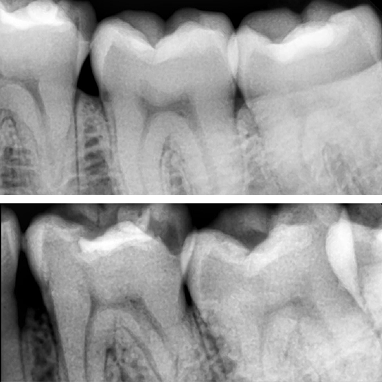

Pernah merasa ngilu di gigi yang bukan main? Rasanya s...

Baca Selengkapnya